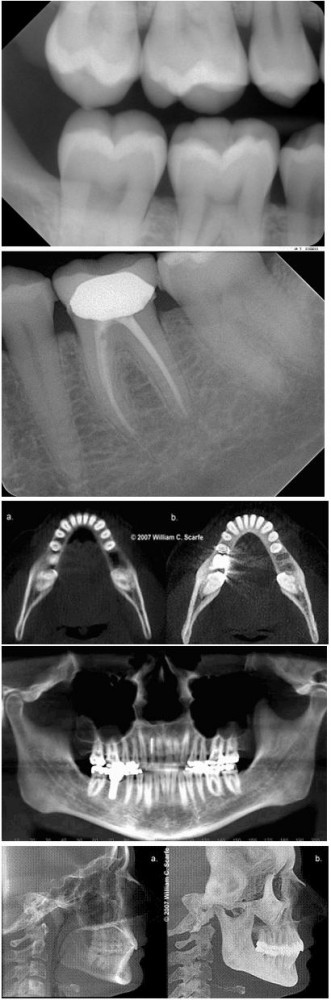

Pentru o mai buna monitorizare a cavitatii bucale  medicul stomatolog recomanda radiografiile dentare.Radiografia dentara reprezinta o imagine a dintilor, maxilarului si tesuturilor inconjuratoare, obtinuta prin expunere la radiatii electromagnetice. Razele X au capacitatea de a penetra corpul si sunt absorbite in diferite grade, in functie de densitatea tesutului. Astfel, structurile dense sunt redate cu alb, tesuturile moi cu nuante de gri, iar cavitatile cu negru, radiografiile aratand ca negativele unor fotografii.

Radiografiile dentare sunt impartite in doua categorii – intraorale si extraorale – in functie de pozitionarea filmului dentar – in interiorul sau in exteriorul cavitatii bucale.

Radiografiile intraorale sunt cele mai obisnuite si redau o imagine detaliata, punind in evidenta cariile, radacinile dintilor, starea osului alveolar si a dezvoltarii dintilor. Este incidenta cu contrastul cel mai bun si de dimensiuni ale imaginii radiologice apropiate de regiunea radiografiata. Principalul deficient consta in faptul ca este parcelara, cuprinzand o regiune limitata si se executa pe un film situat endobucal (in interiorul gurii) ceea ce este uneori mai greu de suportat de catre pacient. Pentru acest tip de radiografie, pacientul nu trebuie sa isi indeparteze bijuteriile.

Radiografiile extraorale dau o imagine de ansamblu, generala a dintilor si mai ales a craniului. Aceste radiografii sunt mai putin detaliate decat radiografiile intraorale, dar pot evidentia zone mult mai extinse. Necesita aparatura roentgen speciala care in decursul anilor a evoluat tehnic foarte mult, imbunatatindu-se imaginea foarte mult, cu o iradiere egala in prezent cu a unei singure radiografii dentare intraorale. Pentru radiografiile extraorale, pacientul trebuie sa isi indeparteze din zona gatului si a capului orice obiect care ar putea sa contina metal deoarece acesta s-ar putea suprapune peste imaginea captata cu interes medical.